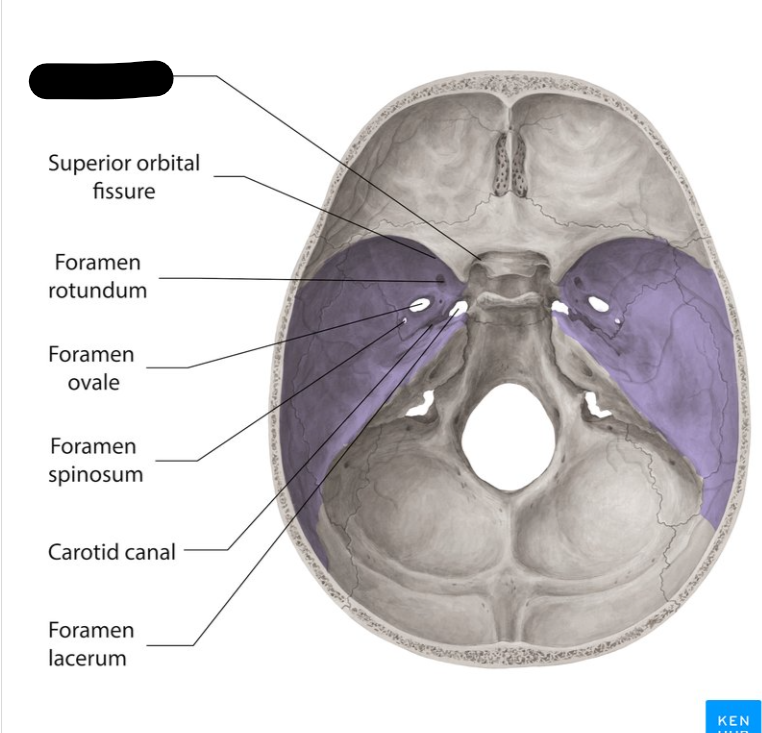

Middle cranial fossa

Foramen rotandum

Foramen ovale

Foramen lacerum

Foramen spinosum

Superior orbital fissure

Optic canal

Carotid canal